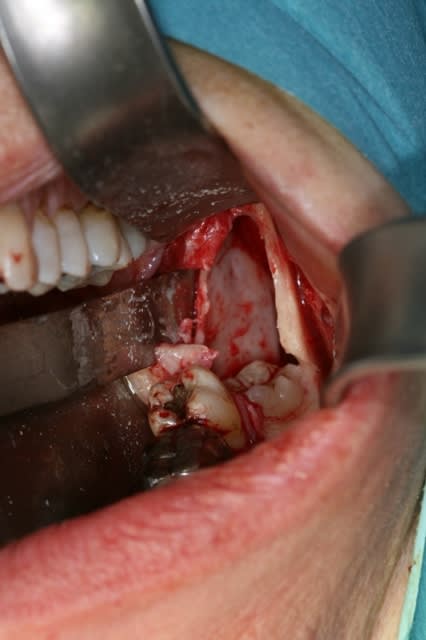

Un petit cas fait ce matin que je partage : kyste péricoronaire de 2,5 cm x 3 cm.

Tout s'est parfaitement passé et la patiente n'a aucune paresthésie. Ouf !

- tu as bien vu le packing sur la photo préop donc effectivement en AG... Certains dirait une AG mais cela peut se faire en local... oui pour l'exérèse mais si tu fractures la mandibule ça devient vraiment galère à gérer en local.

- non je n'ai pas encore l'anapath mais vu la lésion monogéodique uniloculaire, il s'agit à 99% d'un kyste péricoronaire de la DDS.